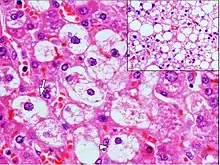

| Micrograph demonstrating marked (macrovesicular) steatosis in non-alcoholic fatty liver disease. Masson's trichrome stain. | |

Steatosis reflects an impairment of the normal processes of synthesis and elimination of triglyceride fat. Excess lipid accumulates in vesicles that displace the cytoplasm. When the vesicles are large enough to distort the nucleus, the condition is known as macrovesicular steatosis; otherwise, the condition is known as microvesicular steatosis. While not particularly detrimental to the cell in mild cases, large accumulations can disrupt cell constituents, and in severe cases the cell may even burst.

Histology

Histologically, steatosis is physically apparent as lipid within membrane bound liposomes of parenchymal cells.[2] When this tissue is fixed and stained to be better viewed under a microscope, the lipid is usually dissolved by the solvents used to prepare the sample. As such, samples prepared this way will appear to have empty holes (or vacuoles) within the cells where the lipid has been cleared. Special lipid stains, such as Sudan stains and osmium tetroxide are able to retain and show up lipid droplets, hence more conclusively indicating the presence of lipids. Other intracellular accumulations, such as water or glycogen, can also appear as clear vacuoles, therefore it becomes necessary to use stains to better determine what substance is accumulating.

Histological section of a mouse's liver showing severe steatosis. The clear vacuoles contained lipid in life; however, histological fixation caused it to be dissolved and hence only empty/clear spaces are seen.

Micrograph of fatty liver showing lipid steatosis. H&E stain.